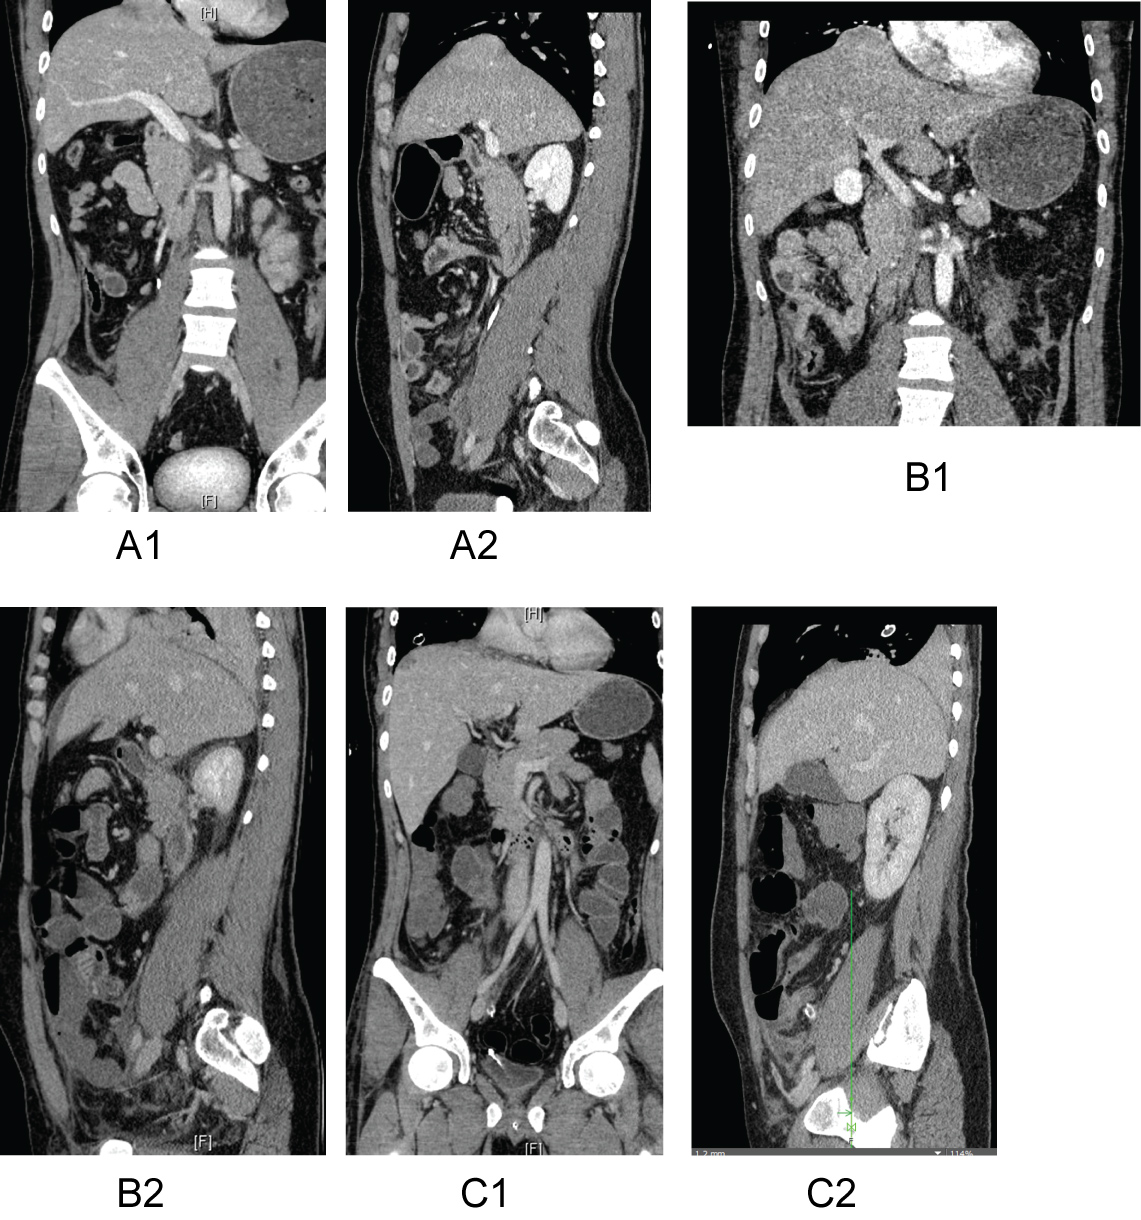

Figure 1: A1 and A2) Initial trauma CT scan with no clear evidence for RTDR although retrospectively one could have suspected a beginning rupture. B1 and B2) After two days, a distinct rupture of the right-side diaphragm could be observed. Coronal and sagittal sections show a liver herniation through the diaphragm into the thorax. C1 and C2) After operative treatment with suture of the diaphragm, no rupture and residual no herniation of the liver can be observed. View Figure 1

Two-stage traumatic right diaphragm ruptures after blunt high-velocity trauma are rare however if they are missed, they are associated with a high mortality rate. Clinical signs are often unspecific with abdominal pain exacerbation and dyspnea. Initial laboratory values like hemoglobin level and lactate appear to stay within range. After initial trauma CT scan, we recommend at least daily sonographic controls of the thorax and abdomen in order to detect signs of hemothorax and free abdominal air or fluid. Further thoracic x-rays may give hints like a raise of the diaphragm, liver herniation and atelectasis (Figure 1).